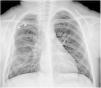

Una niña de cinco años se presentó a consulta con tos y dificultad respiratoria de una semana de evolución. Sin enfermedad conocida, con examen físico anodino. La radiografía anteroposterior de tórax evidenció una costilla con orientación anómala en el hemitórax superior derecho (fig. 1). La evaluación se amplió con una tomografía computarizada (TC) torácica de dosis baja sin contraste. La TC reveló la presencia de una costilla intratorácica bífida que se extendía al parénquima pulmonar (fig. 2, vídeo). Como los síntomas eran leves, se inició tratamiento conservador y se programó una visita de seguimiento.

La costilla intratorácica, que también se conoce como síndrome de la costilla deslizante, es una anomalía extremadamente rara de la caja torácica en la que una costilla normal, supernumeraria o bífida está situada en la cavidad torácica1. La clínica puede incluir dolor punzante o sordo, dificultad respiratoria o falta de aliento y un bulto o masa palpable cerca de la costilla involucrada.1 Su manejo suele consistir en una combinación de medidas conservadoras y, en casos graves, intervención quirúrgica2. La TC torácica permite visualizar de manera precisa la forma tubular y la curvatura de la costilla intratorácica y guiar la cirugía1,2.